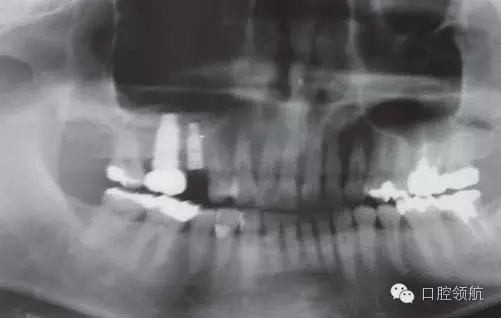

圖7 手術(shù)后的曲面斷層片。

術(shù)后8個(gè)月未見異常(圖8),并完成( 左上第五顆牙) 的上部修復(fù)(圖9)。

圖8 術(shù)后8個(gè)月的牙片。兩顆種植體愈合良好。

圖9 術(shù)后8個(gè)月戴入上部修復(fù)后的曲面斷層片。